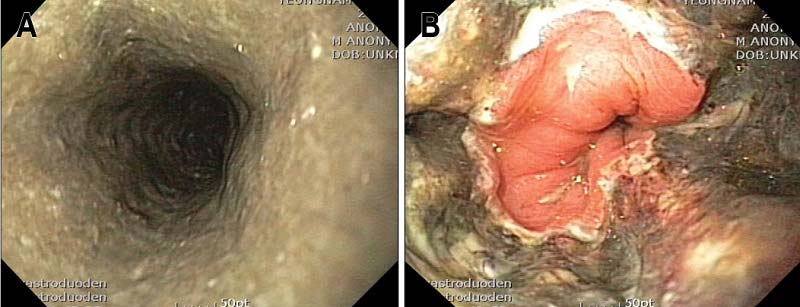

국내 영남대 의대 의료진이 48세 남성 B씨에게 단순 알코올 과섭취로 인해 나타난 급성 괴사성 식도염을 보고한 바 있다. 평소 일주일에 소주 18병 정도의 알코올을 섭취해온 B씨는 하루 세 차례의 피 섞인 구토, 삼킴곤란 증상으로 병원을 찾았다. 병원을 찾은 당일 상부위장관 내시경을 했더니 식도 전체에서 검은 점막이 관찰됐다. 다행히 수액 보충, 양성자 펌프 억제제 등으로 치료해 증상이 크게 호전됐고, 합병증 없이 퇴원했다. 의료진은 "과량의 알코올을 섭취하면 식도 점막 저혈류가 발생하면서 식도가 괴사할 수 있다"며 "B씨 사례를 통해 기저질환 없이 음주와 연관돼 급성 괴사성 식도염이 발생할 수 있다는 사실을 알 수 있다"고 설명했다. 이 사례는 '대한소화기학회지'에 게재됐다.